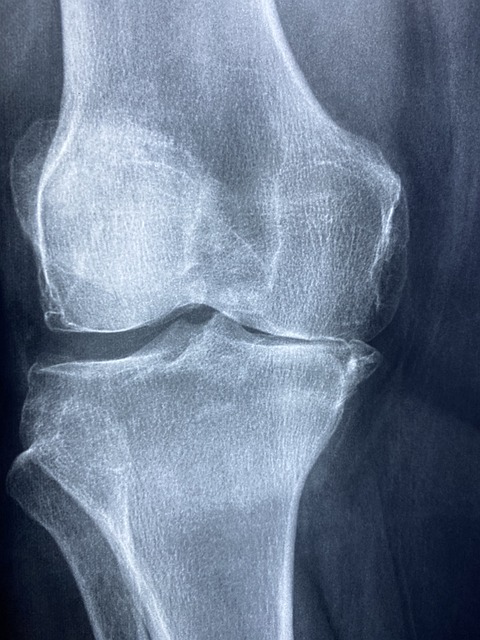

- X-레이: 슬개골과 대퇴골 사이의 정렬 상태를 평가하고, 뼈의 구조적 문제가 있는지 확인합니다. 그러나 X-레이는 연골 자체는 보여주지 않습니다.

- 자기 공명 영상(MRI): MRI는 연골의 상태를 보다 상세하게 평가할 수 있으며, 연골연화증 진단에 특히 유용합니다. 연골의 손상 정도와 연화 상태를 정확히 보여줍니다.

- 관절경 검사: 드물게, 의사는 관절경을 사용하여 무릎 내부를 직접 검사할 수 있습니다. 이 방법은 연골의 손상을 직접 관찰하고 평가할 수 있어 정확한 진단을 제공합니다.